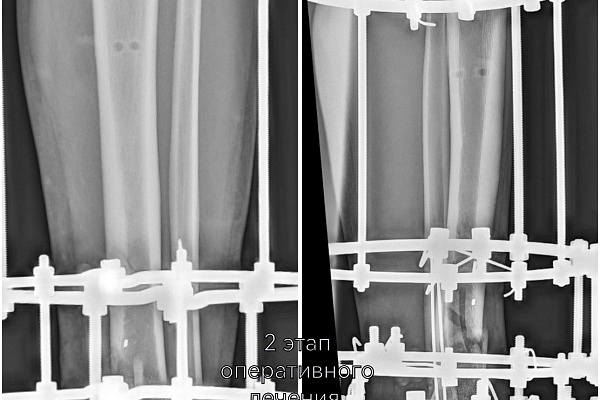

Цель первого этапа хирургического лечения - жизнеспособность конечности – была достигнута. Цель второго этапа – опороспособность. К нему приступили, убедившись, что ранний послеоперационный период протекает благополучно, без осложнений.

-На втором этапе первично установленный стержневой аппарат демонтирован и выполнен окончательный остеосинтез аппаратом Илизарова. На сегодняшний день это самый надежный и управляемый вариант. Данный вид фиксации позволяет проводить раннюю реабилитацию и передвигаться с нагрузкой на поврежденную ногу. Послеоперационный период проходит спокойно, мужчине назначено комплексное восстановительное лечение, включающее физиотерапевтические процедуры и занятия ЛФК, - объясняет лечащий врач Юрия, травматолог-ортопед Артём Мещеряков, выполнивший второе вмешательство.